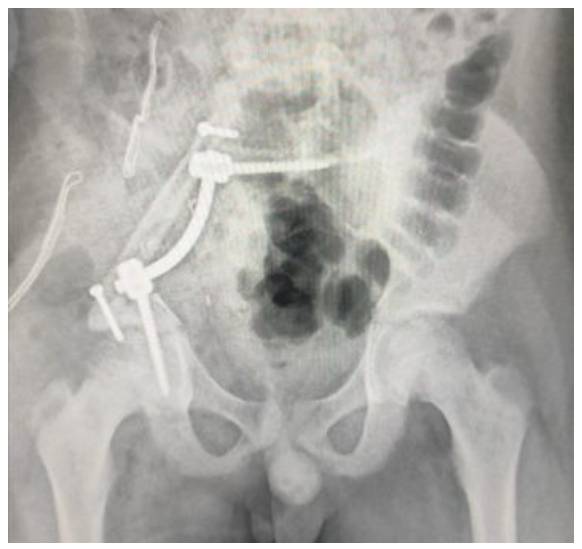

Neoadjuvan kemoterapi sonrası internal hemipelvektomi ve fibula ve lumbopelvik fiksasyon ile rekonstrüksiyon işlemi uygulandı

Ameliyat Esnası: Rezeksiyon sonrası nörovasküler yapıların korunduğu, fibula ve rod/vida ile rekonstrüksiyon uygulanımı görülmekte

Ameliyat Sonrası: İnternal hemipelvektomi sonrası fibula ve rod/vida ile lumbopelvik fiksasyon uygulanımı görülmekte